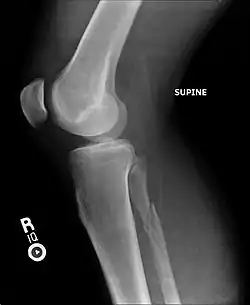

Ankle radiographs are used to detect widening of the tibiofibular syndesmosis or medial clear space. The medial clear space is the area between the talus of the ankle and the medial malleolus. Damage to the deltoid ligament and syndesmotic ligaments result in mortise instability, causing the talus to laterally shift and widen the medial clear space.[4][12] A clinical study, conducted in 2006 and published in the Journal of Bone and Joint Surgery, found that the medial clear space size of a normal ankle and an injured ankle measured at 4 millimetres and 5.4 millimetres in length respectively.[11] To confirm diagnosis, full-leg radiographs are used to inspect for fractures of the proximal fibula and widening of the interosseous clear space (or tibiofibular clear space). The interosseous clear space is the area between the medial side of the fibula and lateral side of the tibia. A peer-reviewed study, published in Injury in 2004, found that an interosseous clear space greater than 10 millimetres indicates diastasis of the syndesmotic ligaments.[4]

If necessary, Computed Tomography (CT) or Magnetic Resonance Imaging (MRI) may also be used to clarify diagnosis. MRI scans can check for interosseous membrane or tibial tubercle damage if high instability of the ankle is diagnosed.[8][11] Arthroscopy may be used to diagnose a syndesmotic lesion but is often not recommended due to operative difficulty.[13] Stress radiographs of the ankle are used to assess the integrity of the deltoid ligament and tibiofibular syndesmosis.[9][13] The size of the medial clear space can also be measured using stress radiography.[11]